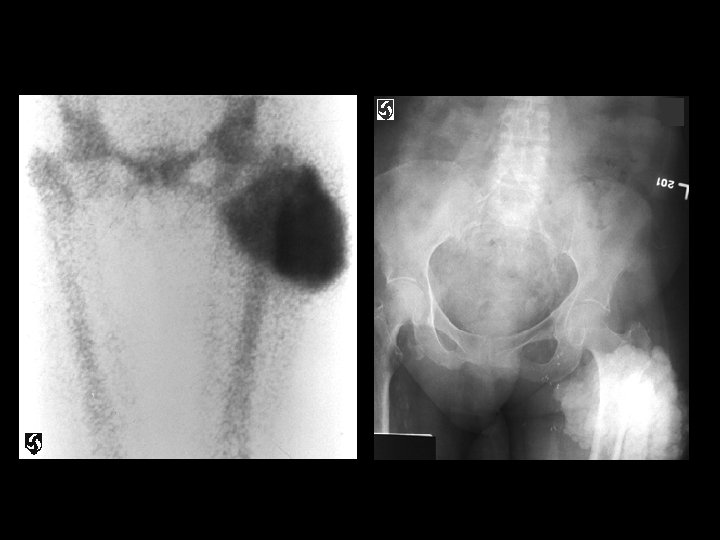

Tumoral calcinosis • Findings: – Intense mass-like uptake about the proximal lateral thigh – Plain film shows soft tissue calcification • ddx: – Myositis ossificans – Heterotopic ossification – Parosteal osteosarcoma